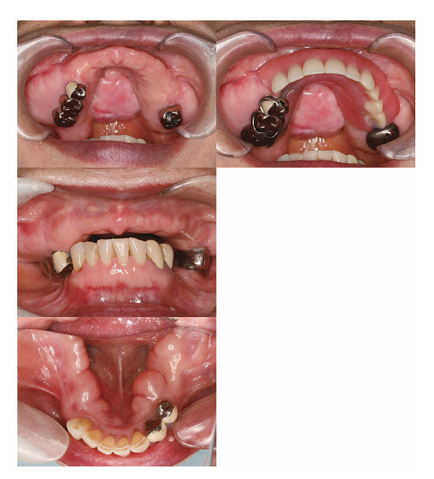

今回、広範囲にわたる骨隆起形成術後の補綴治療の1 例を経験したので報告する。患者は65歳の女性で、2013年に左側下顎歯肉の腫れを自覚して当科を受診した。口腔扁平苔癬と診断されて加療し、2015年まで経過観察を行っていた。2018年、義歯の装着困難を主訴に再受診した。口蓋正中部、上顎臼歯部頬側、下顎舌側に、粘膜表面は正常で、周囲との境界は明瞭な骨様硬の膨隆を認めた。上顎残存歯はすべて著しい挺出が認められ、義歯を装着するために必要な空間が不十分であった。広範囲にわたる顎骨外骨症、義歯装着困難による審美障害と診断した。広範囲にわたる骨隆起形成が必要なことから、外科的処置を行う口腔内科と連携して補綴主導型の治療計画を立案した。

<術前の口腔内写真>